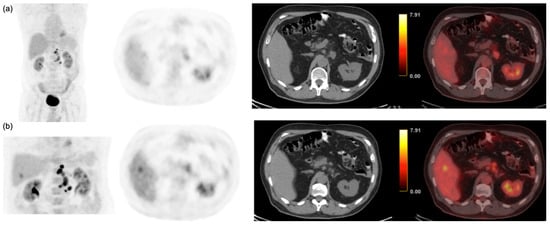

3.2. Per-Patient Performance of Early and Delayed Imaging

3.3. Semi-Quantitative and Per-Lesion Analysis

| Early | 50 | 61 | 6 | 7 | 87.7% | 91.0% | 0.04 | 88.1% |

| Delayed | 57 | 63 | 4 | 0 | 100.0% | 94.0% | 96.2% |

| CRLM | SUVmean | 5.3 ± 2.2 | 5.5 ± 3.0 | <0.001 |

| (n = 168) | SUVmax | 8.6 ± 5.4 | 9.7 ± 7.1 | <0.001 |

| TNR | 3.5 ± 2.5 | 5.4 ± 3.8 | <0.001 | |